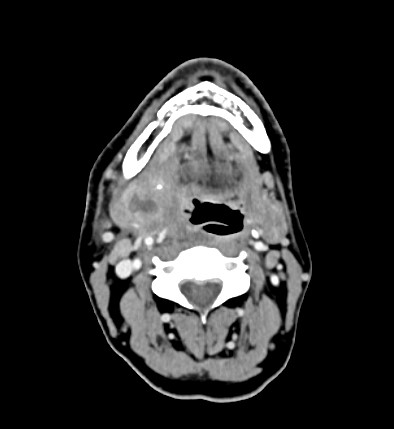

Le CT-scanner cervical (cf. image) confirme une sialadénite abcédée de la glande sous-mandibulaire droite secondaire à un sialolithe proximal du canal de Wharton, sans complication vasculaire.

Image proposée par Hôpital de La Tour.